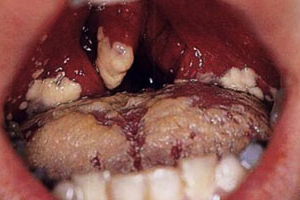

На стадии острого кандидозного воспаления в ротоглотке появляются многочисленные белые пятна, расположенные на небных дужках, миндалинах, язычке мягкого неба, глотке и других участках. После механического удаления налета на слизистой могут образовываться кровоточащие язвы, что приводит к отеку тканей. В зонах наибольшего поражения слизистой наблюдается отслоение эпителия.

Важно! Белый налет указывает на наличие дрожжеподобных грибков, в то время как зеленый или желтоватый налет свидетельствует о плесневых грибах.

В большинстве случаев кандидозное воспаление слизистых оболочек можно выявить при визуальном осмотре горла. У детей грудного возраста лимфаденоидная ткань рыхлая, и творожистый налет может напоминать гнойные образования. Поэтому для точного определения типа заболевания необходимо провести микробиологическое исследование мазка из зева.